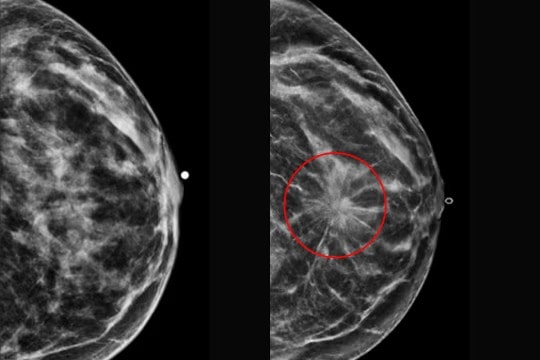

Dự đoán ung thư vú từ một tấm nhũ ảnh

Hiện nay, các nhà nghiên cứu và công ty công nghệ y tế đang phát triển những mô hình AI có khả năng dự đoán nguy cơ ung thư vú trong tương lai gần của phụ nữ – và thậm chí là nguy cơ mắc ung thư phổi cùng nhiều bệnh khác. Các thuật toán này được “huấn luyện” trên dữ liệu chụp nhũ ảnh (mammogram) của hàng trăm nghìn bệnh nhân trong quá khứ – trong đó có những người sau này đã phát triển ung thư vú – nhằm xác định sớm những người có nguy cơ cao, trước cả khi căn bệnh biểu hiện rõ bằng mắt thường.

Mô hình AI của Clairity được thiết kế để dự đoán nguy cơ ung thư vú trong vòng 5 năm chỉ từ một tấm nhũ ảnh định kỳ. Lehman cho biết mô hình đã được huấn luyện trên hơn 400.000 nhũ ảnh có sẵn trong hồ sơ bệnh viện, được đối chiếu với tình trạng ung thư của người phụ nữ sau 5 năm. Nhờ vậy, AI có thể phát hiện những mẫu hình vi mô trong mô vú mà giới nghiên cứu tin rằng là dấu hiệu báo trước của ung thư – những dấu hiệu tinh vi đến mức mắt người chưa thể phân biệt được.

Khi thử nghiệm công cụ này, nhóm nghiên cứu nhận thấy AI còn có thể dự đoán được tuổi, tình trạng mãn kinh, thậm chí việc từng sinh con của người phụ nữ – chỉ qua một tấm nhũ ảnh. Lehman nói: “Cả hành trình cuộc đời người phụ nữ đều được khắc ghi trong hình ảnh mô vú của họ”.